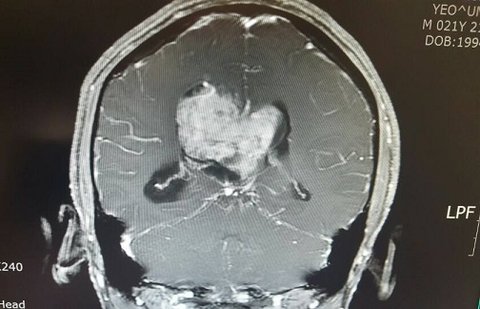

( 뇌종양 수술 전후 MRI 사진을 같이 올리겠습니다.  수술 전 사진 가운데 보이는 하얀색 덩어리가 뇌실에 있는 지름 6cm짜리 종양입니다. )